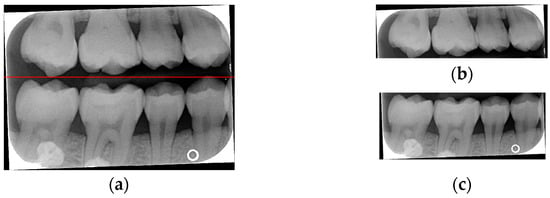

Due to angular issues in a BW, horizontal and vertical lines may not fully separate the teeth. This study addresses this by rotating and binarizing images multiple times to enhance the contrast between teeth and gaps. High-contrast images allow for accurate identification of tooth gaps through pixel horizontal projection as shown in Figure 4a. The image is divided horizontally into three parts, masking the upper and lower sections to focus on the middle, like the upper and lower sides of the red box in Figure 4b are masked. The valleys of the projection line in this region are identified as the x-minimum value, and the y-coordinate of the valley represents the vertical height separating the upper and lower rows of teeth after rotation. Additionally, during each rotation, a projection is made to identify the trough position in the middle of the image. The trough values (x-minimum) at each angle are compared to determining the optimal rotation angle for horizontal segmentation. Initially, the image is rotated within a range of plus or minus 15 degrees, in increments of 5 degrees. By comparing the trough values at each angle, the most suitable rotation angle for horizontal cutting is identified, as shown in Figure 4b.

Figure 4.

Horizontal projection of the rotated image. (a) BW rotated +5 degrees; (b) BW rotated +10 degrees.

According to Table 1. After performing small-angle rotations and comparing the trough values at each angle, it was determined that the lowest trough value (x = 36) occurs at a rotation of 11 degrees, which is lower than the trough value (x = 40) obtained at the initial rotation of 10 degrees. Therefore, it can be concluded that a positive 11 degrees is the most suitable rotation angle for this BW, which is more favorable for subsequent horizontal segmentation. If a smaller rotation angle is used from the beginning to find a suitable angle, multiple calculations will be required within the same range of angles. However, by gradually rotating the image in two steps, one large angle (5 degrees) and one small angle (1 degree) to obtain the most suitable rotation angle, we achieve the same result and find out the suitable angle more quickly. After rotating the image of each BW to a suitable angle, the height of the trough (y-value) is found. The height of the plumb coordinates of the troughs are found and the horizontal line separating the upper and lower jaws is plotted using the height of these coordinates. This allows the entire BW to be divided into upper and lower rows of teeth; the specific segmentation result is shown in Figure 5.